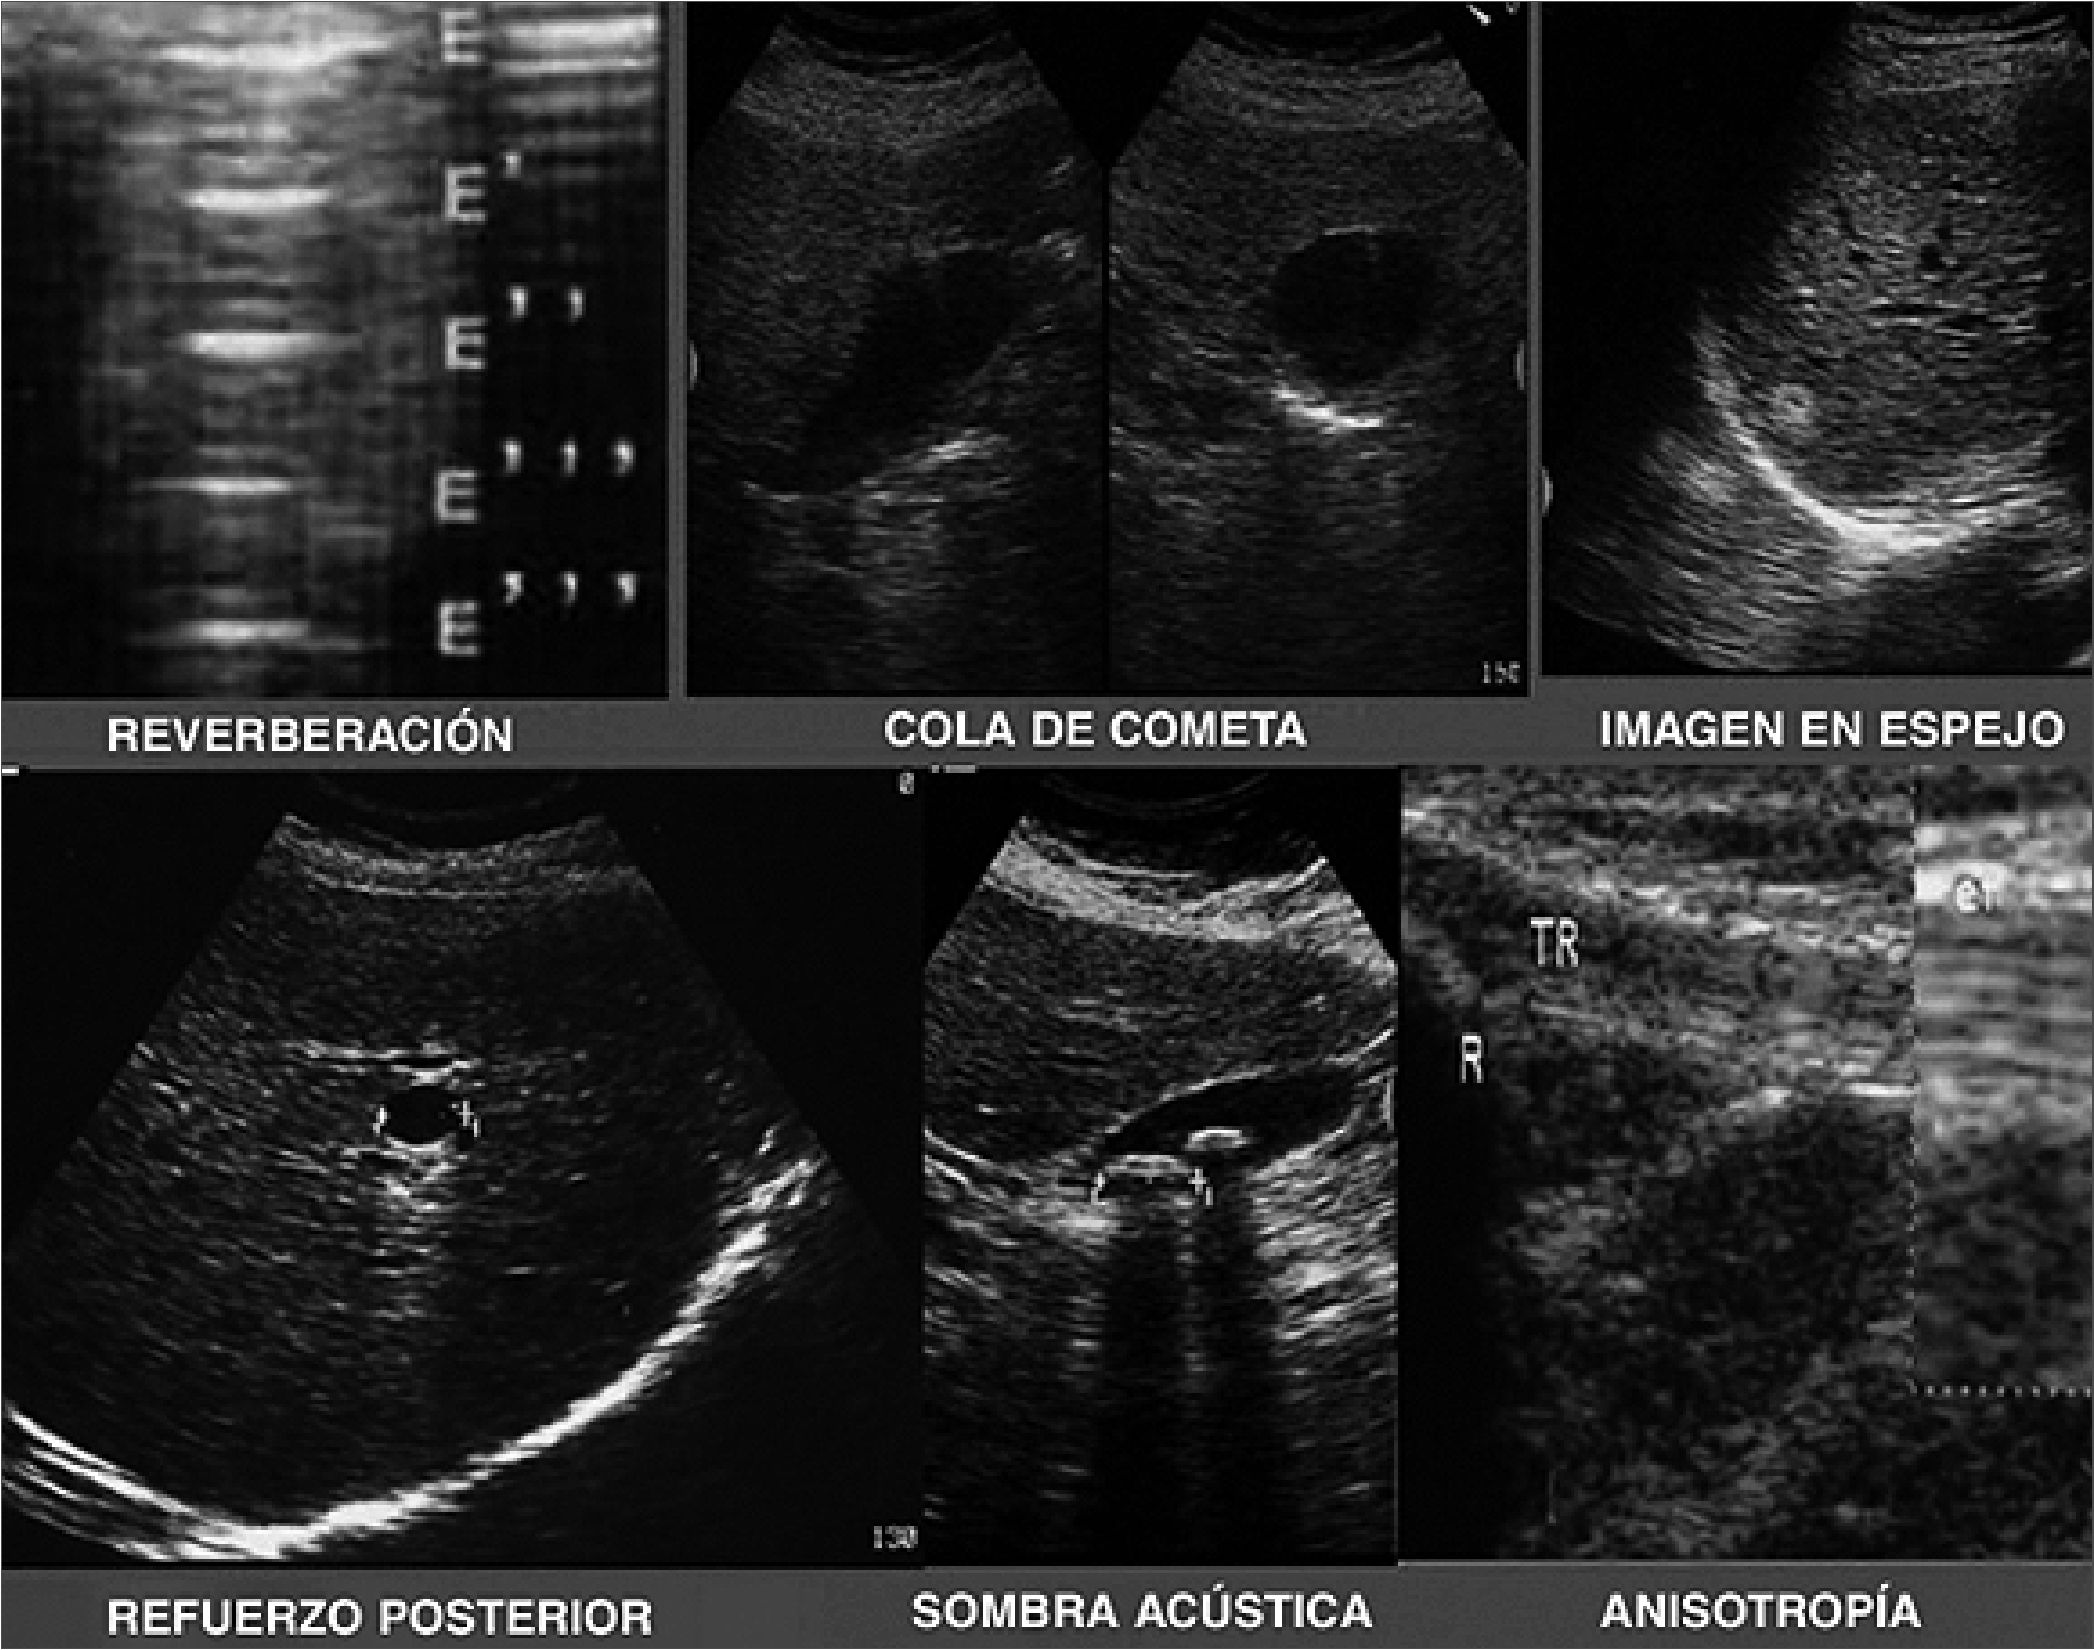

Se denominan artefactos a las interacciones de los tejidos con el ultrasonido que generan imágenes no deseadas.

– Reverberación: Se refiere a la imagen obtenida cuando el ultrasonido rebota entre una estructura o material y el transductor de forma continua. Podemos encontrar este artefacto en la presencia de gas o metal. Este fenómeno puede producir una imagen llamada “cola de cometa” por la figura que produce al interactuar con algunos materiales.

– Imagen en espejo: Ocurre cuando el eco del ultrasonido rebota en una estructura curva como sucede en la calota craneal.

– Refuerzo posterior: Es el resultado del paso de los ecos a través de una estructura que contiene líquido en su interior (Ej. quistes) aumentando la amplitud de las ondas y generando una imagen hiperecoica en la zona posterior de la estructura (Figuras 4 y 5).

Figura 5. Artefactos ecográficos[1].

– Sombra acústica: Es la imagen hipoecoica que aparece detrás de una estructura hiperecogénica (ej. huesos).

– Anisotropía: Una sustancia anisotrópica es aquella que muestra propiedades diferentes dependiendo de la dirección en la que se aplica el ultrasonido, por lo general los tendones, por lo cual se deben evitar abordajes oblicuos a menos de que se quieran diferenciar estructuras (grasa vs tendones)[1],[15].